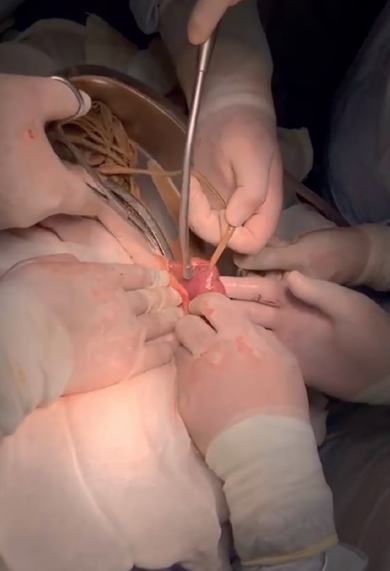

Por lo que se decidió la realización de laparotomía exploradora el 10-05-2021, con los siguientes hallazgos transoperatorios: líquido libre en cavidad abdominal de aproximadamente 200 cc de características purulentas, asas intestinales dilatadas. Presencia de bezoar de material textil y plástico a 10 cm de válvula ileocecal, intestino grueso con áreas de isquemia los cuales recuperan coloración, con múltiples nadas de fibrina. Presencia de isquemia y parches de necrosis a 50 cm de válvula ileocecal. Catéter Tenckhoff disfuncional, Obtendiendo 200 cc de sangrado (figuras 4, 5, 6 y 7). integrando el diagnóstico de oclusión intestinal secundario a bezoar de textiles y plásticos, realizando lavado de cavidad abdominal, creación de ileostomía y retiro de catéter Tenckhoff.

Figura 4 Enterotomía realizada a nivel de íleon para la extracción de bezoar de telas.

Figura 5 Enterotomía realizada con aspiración de material fecaloide junto con extracción de bezoar de textiles y plástico.

Figura 6 Obtención de material textil proveniente de compresas, así como múltiples plásticos provenientes de bolsas de diálisis peritoneal.

Figura 7 Obtención de material textil proveniente de compresas, así como múltiples plásticos provenientes de bolsas de diálisis peritoneal.